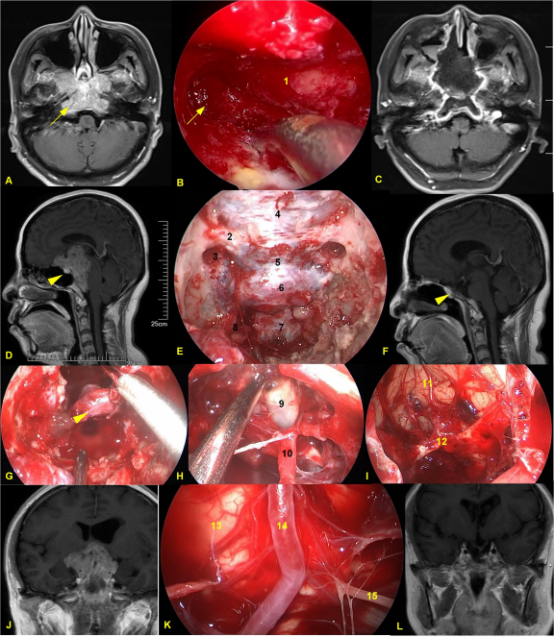

图1. A-C 向蝶鞍下方发展的侵袭骨质的垂体腺瘤。A、C 术前、术后轴位T1增强MRI。B术中所见,向侧下方磨除被肿瘤侵袭的颈静脉结节骨质。D-L 广泛侵袭颅底的垂体腺瘤。D、F术前、术后1年矢状位T1增强MRI。E 术中骨窗显露范围。G 肿瘤切除后正常垂体予以保留。H 肿瘤切除后第三脑室开放。I肿瘤切除后显露额叶及前交通动脉复合体。K 斜坡后方肿瘤切除后显露脑干及桥前池。J、L术前、术后1年冠状位T1增强MRI。1斜坡;2右侧视神经管;3视神经管-颈内动脉隐窝;4蝶骨平台硬膜;5鞍结节硬膜;6 鞍底硬膜;7斜坡硬膜;8 斜坡旁段颈内动脉;9第三脑室;10 垂体柄;11额叶直回;12 前交通动脉复合体;13脑干;14基底动脉;15左侧外展神经。黄色箭头所示为被肿瘤侵袭的颈静脉结节;无尾黄色箭头所示为正常垂体。